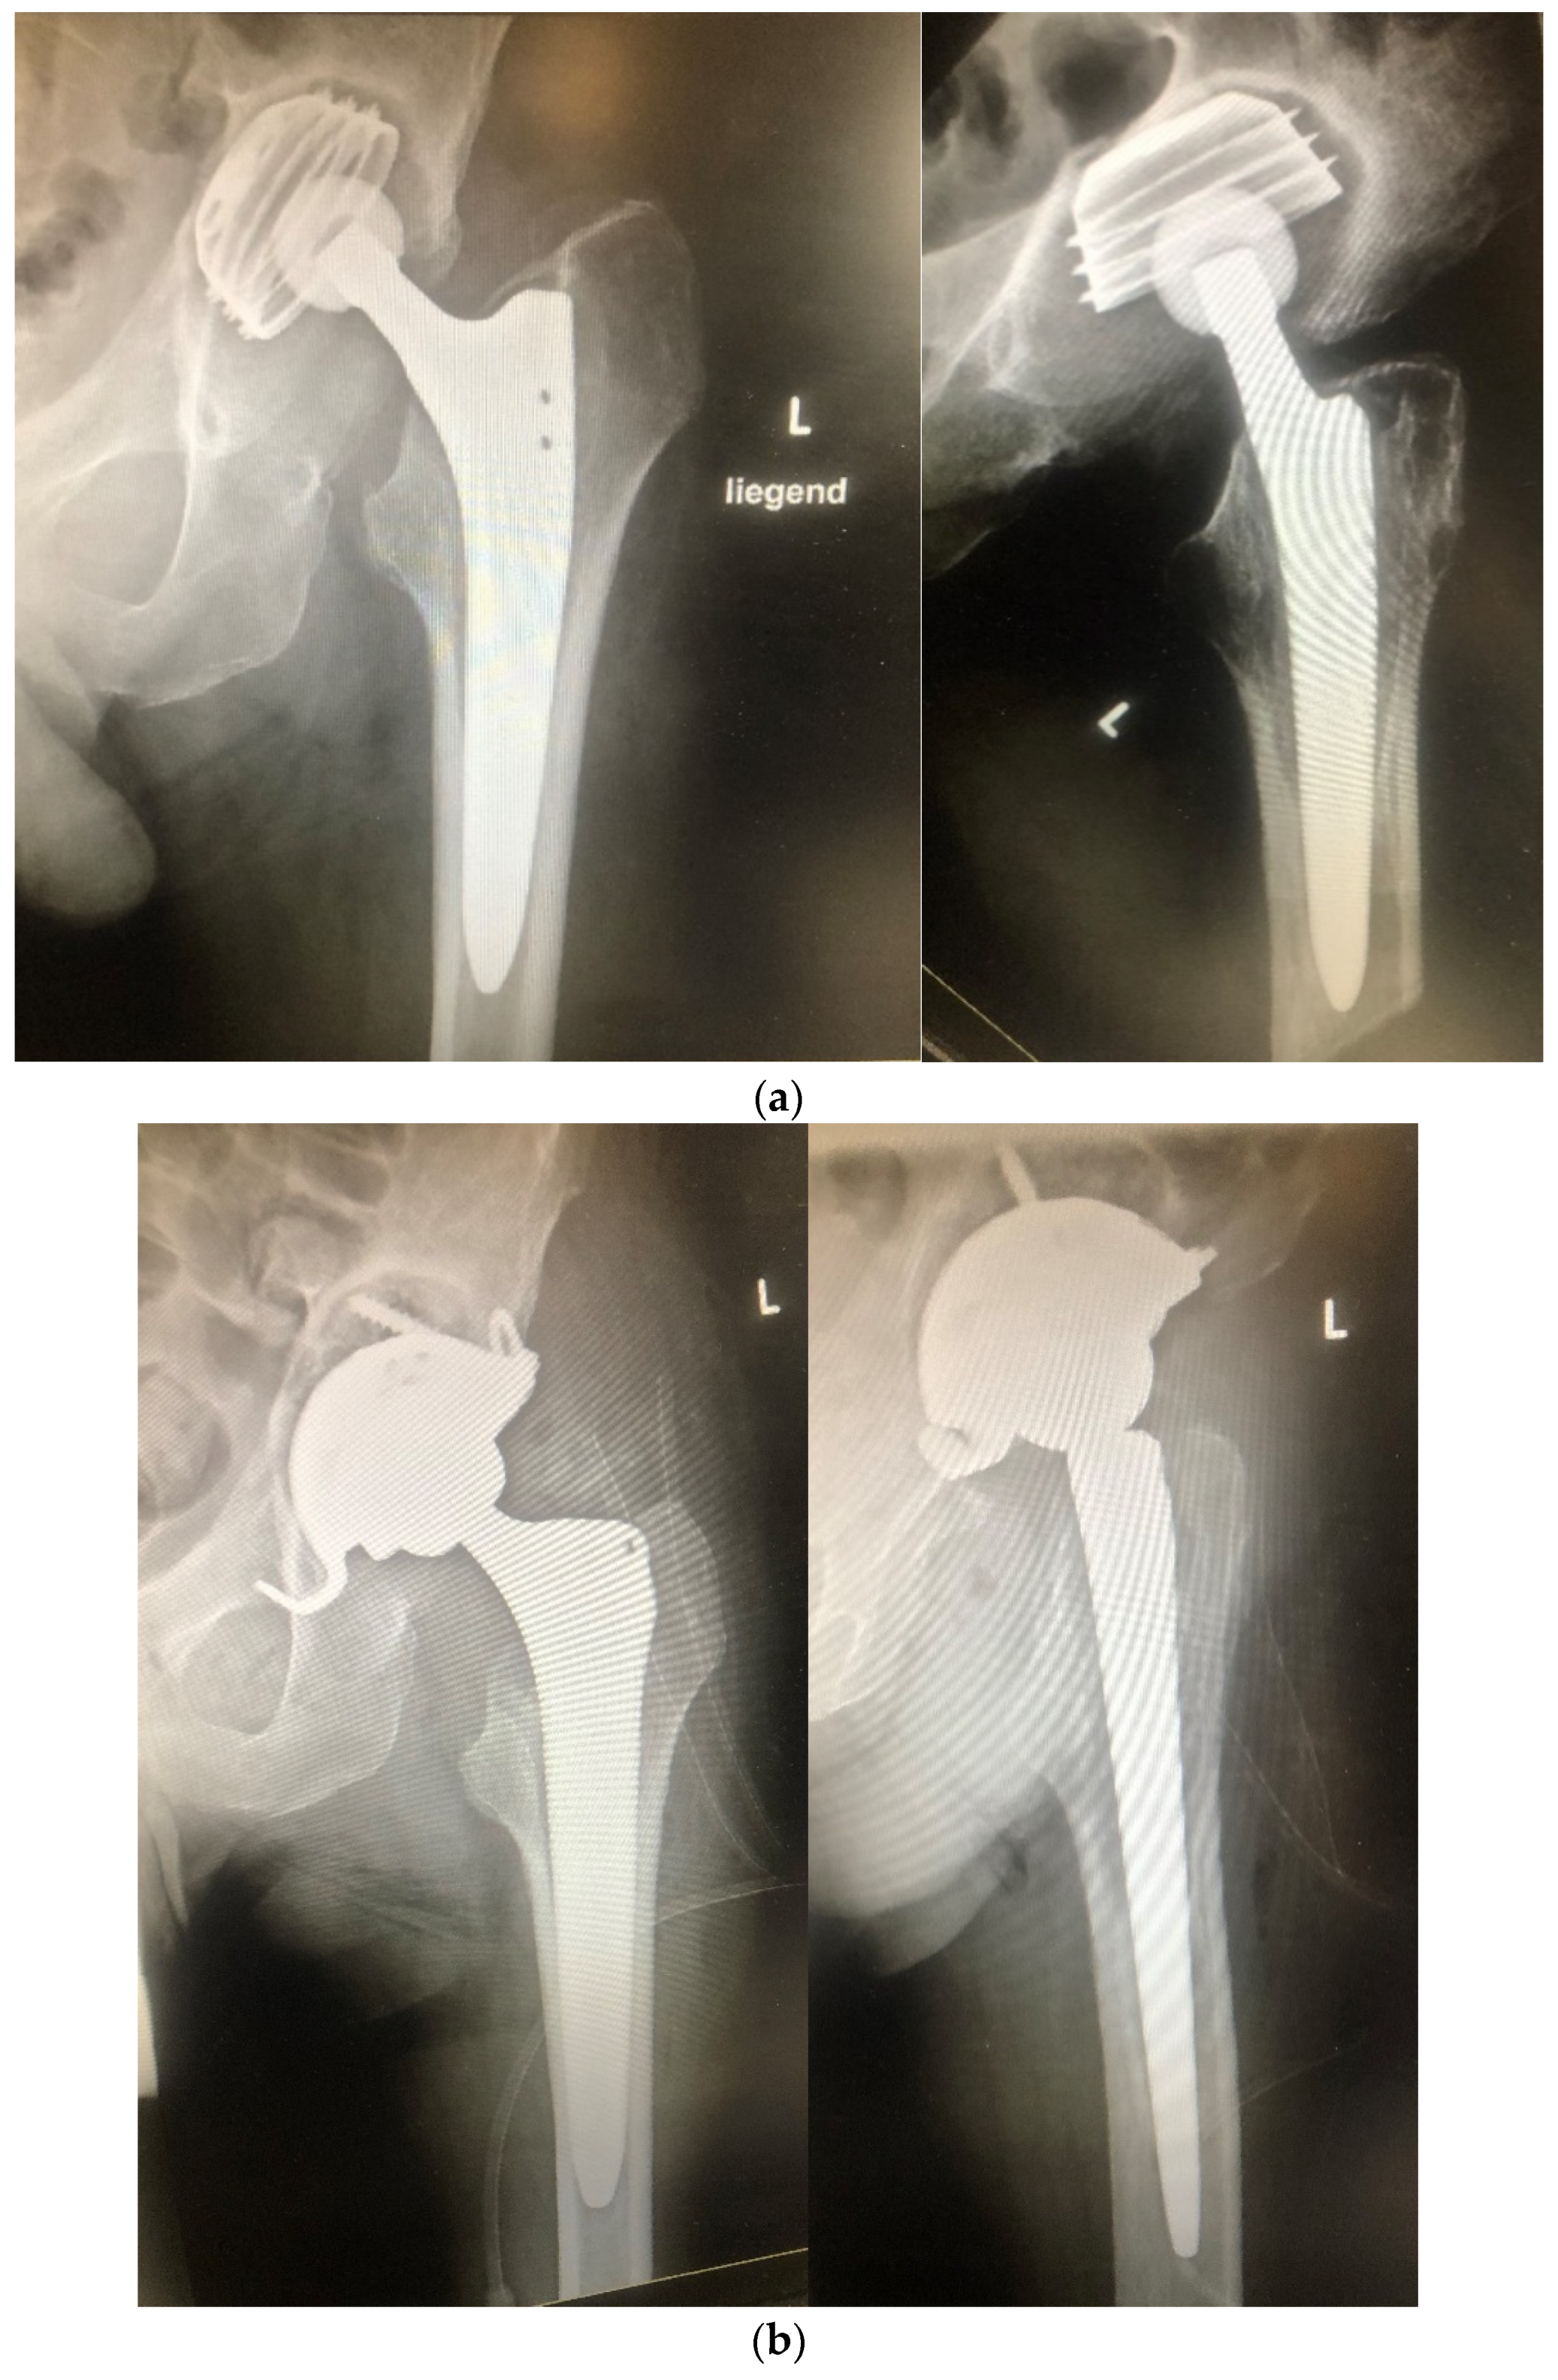

| Hip Joint | 38 (54.3%) |

| Volume antibiotic-impregnated allograft bone (cm3) | 92.2 ± 27.8 (40–202) |

| Cementless prosthesis implantation | 49 (70%) |